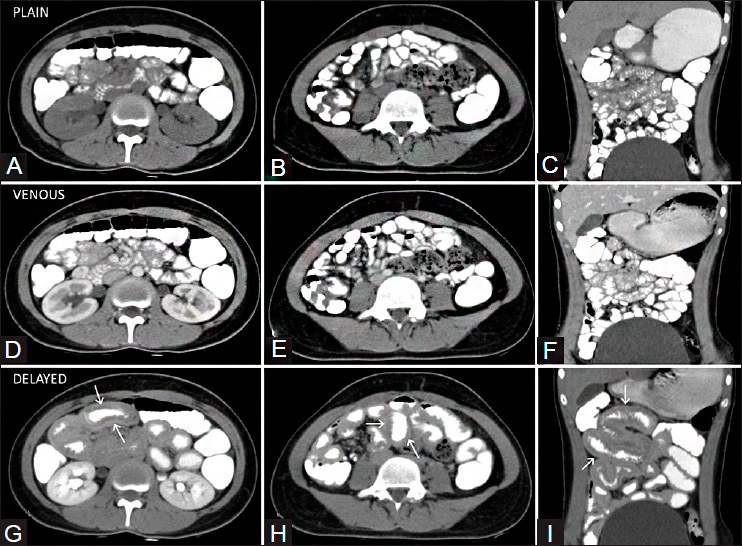

Компьютерная томография

О, это рентген на максималках.

Послойная непрерывная съёмка. Принцип точно такой же, как в рентгене, но количество экспозиций больше. Можно делать снимки как 2д, так и 3д.

Результаты:

Для чего применяется:

КТ органов брюшной полости

Наличие изменений, образований, гематом, абсцессов, инородных тел, свищей (патологического соединения орган-орган, орган-внешняя среда). Повреждение костей. Наличие тромба/ов в сосудах. Камешки можно увидеть.